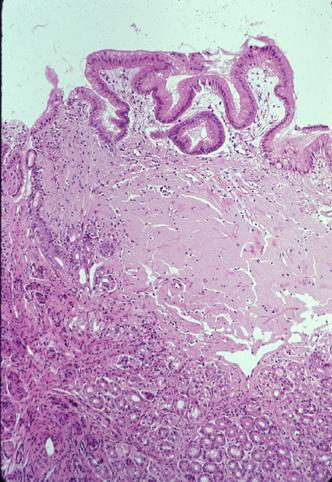

A case of gastric amyloidosis resembling IIc type early gastric cancer.

Inflammatory or ulcerative disease / lesions/Amyloidosis

Stomach/Antrum

Histology